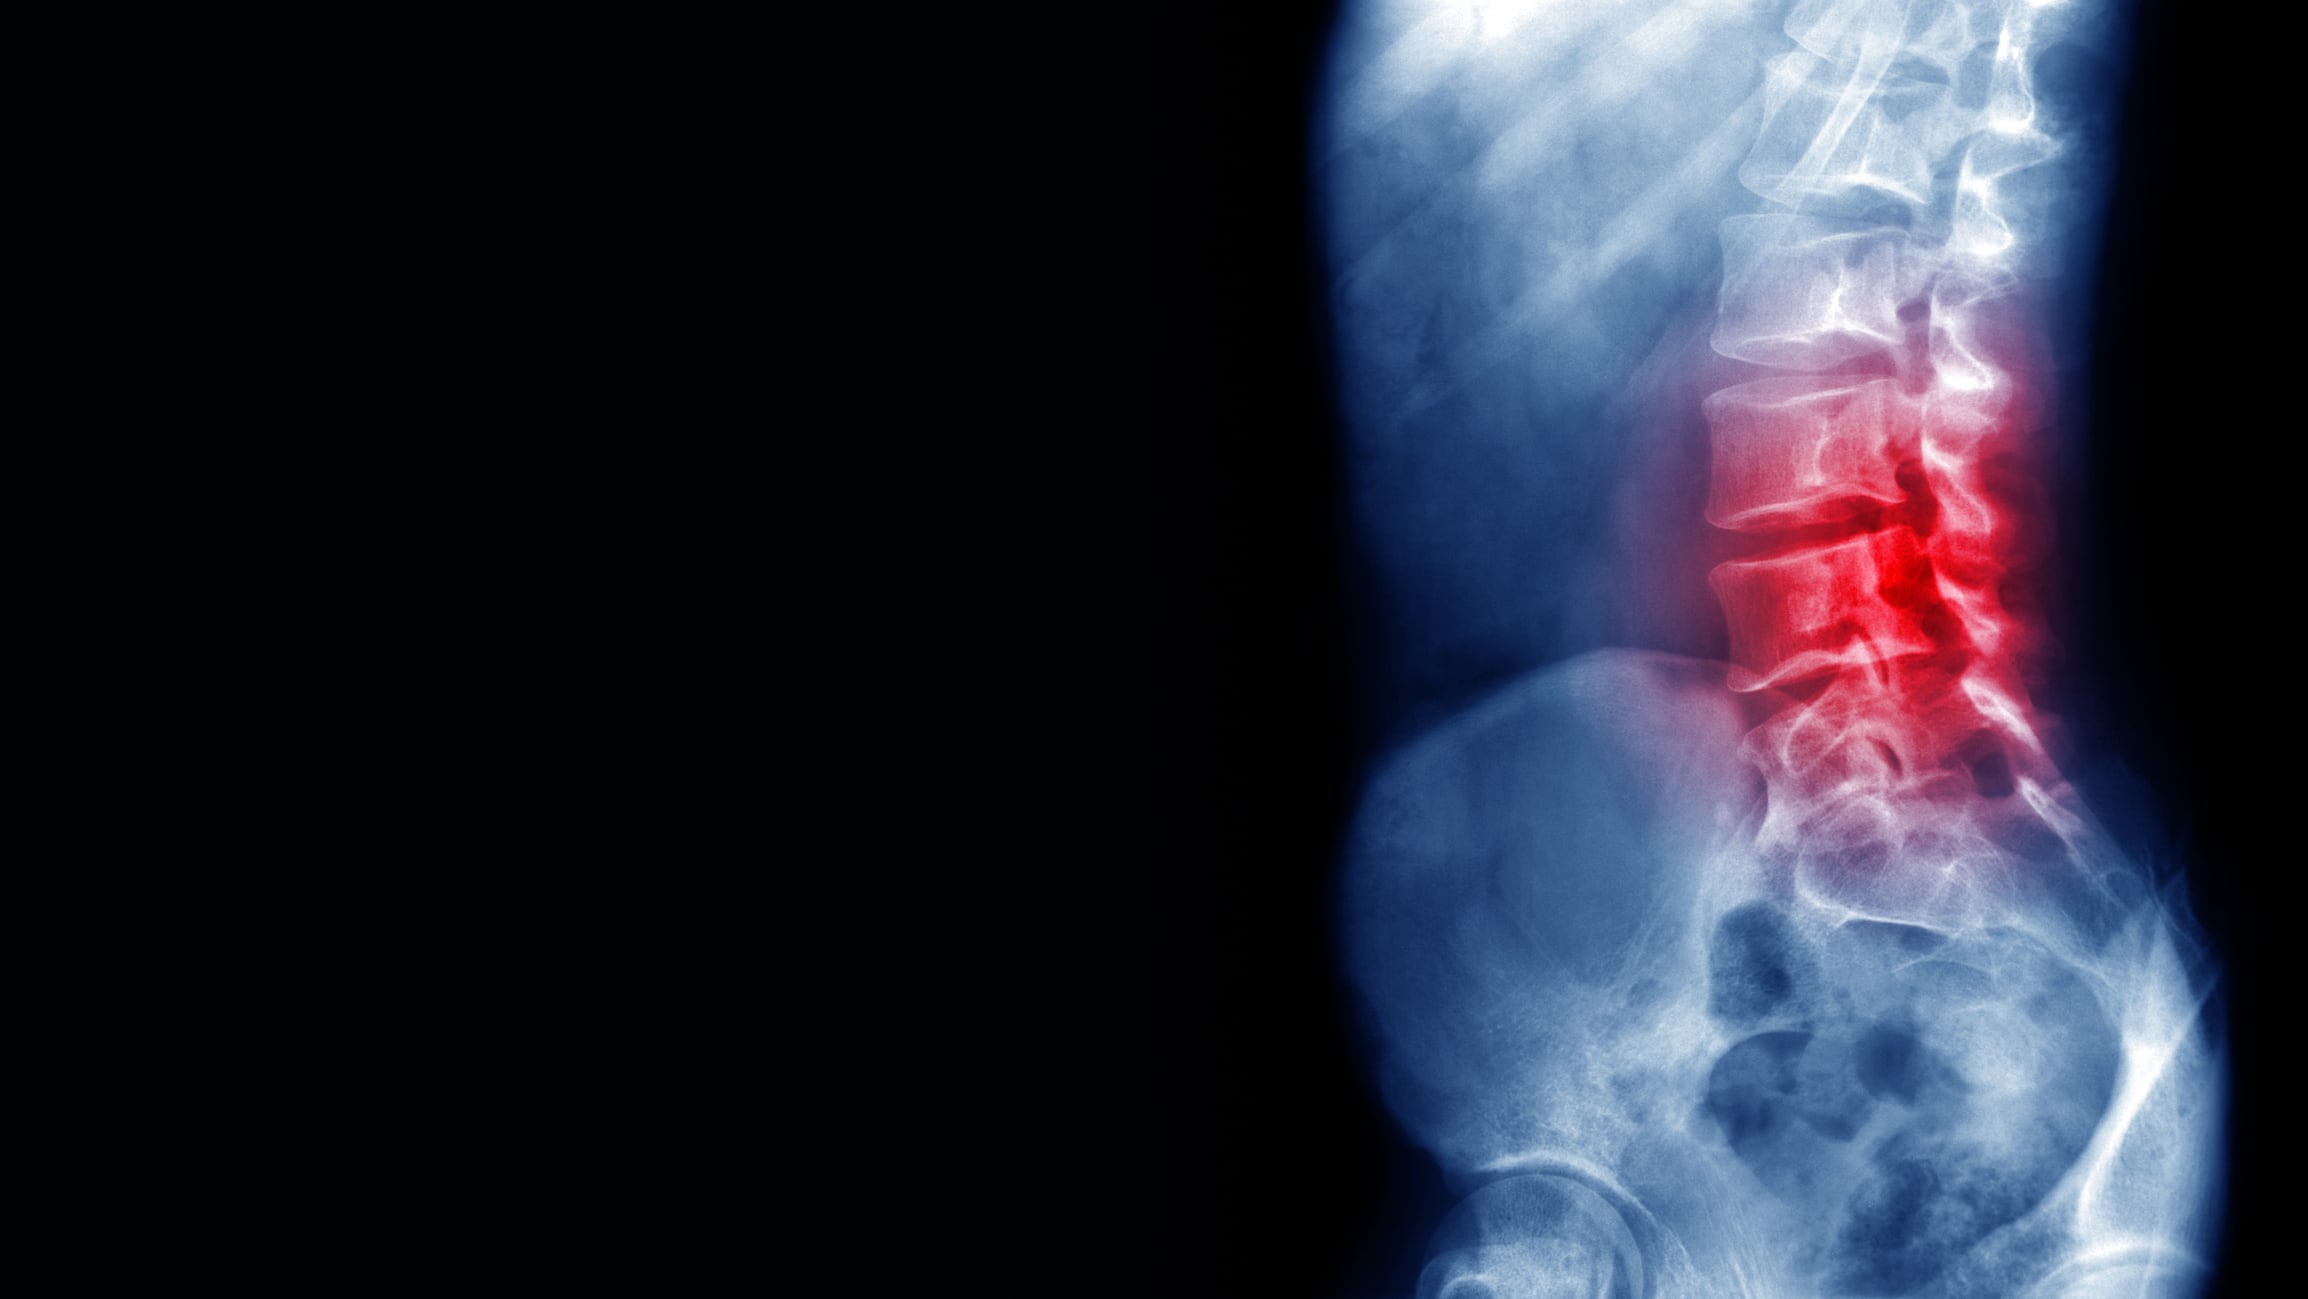

¿Es normal tener dolor de espalda de manera constante?

El dolor de espalda es una de las razones más comunes por las que las personas buscan atención médica o faltan al trabajo. Normalmente, esta dolencia se puede extender hacia la pierna y puede dificultar acciones como agacharse, girarse, levantar peso, estar de pie o caminar. Sin embargo, en muchos casos es un dolor que puede desaparecer en dos días y sin necesidad de solicitar atención médica.

De acuerdo con Medline Plus, sitio web de la Biblioteca Nacional de Medicina de Estados Unidos, cuando el dolor de espalda es fuerte, se trata de un lumbago agudo que concentra el dolor en la región lumbar. De hecho, esta dolencia se siente cuando se presenta rigidez en la espalda, hay disminución del movimiento de la región lumbar y existe una mayor dificultad para ponerse de pie y permanecer derecho.

Por lo general, el lumbago agudo es causado con mayor frecuencia por una lesión repentina en los músculos y los ligamentos que sostienen la espalda. Asimismo, puede ser causado por espasmos musculares o distensión o desgarro en músculos y ligamentos, pero también se relaciona con los siguientes problemas de salud:

En la mayoría de los casos, los especialistas en salud orden exámenes como radiografía, tomografía computarizada de la región lumbar y resonancia magnética de la región lumbar, para diagnosticar el problema y así prescribir el tratamiento adecuado.